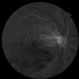

- inferotemporal arcade, superotemporal arcade

- 47-year-old female who came in with blurring of vision of the right eye of 2 weeks duration. She is hypertensive with poor control, taking Amlodipine irregularly. Denies any cardiac problem non-diabetic. Vision upon presentation was 20/400 (OD), 20/20 (OS) . Early arterial phase shows beginning asymmetrical perfusion of the supero-temporal arcade supplying the macula. Infero-temporal arcade shows no perfusion.